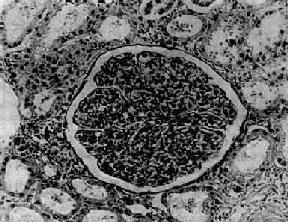

图12-7 弥漫性毛细血管内增生性肾小球肾炎

肾小球内细胞数量增多,系膜细胞和内皮细胞增生并有少量中性白细胞浸润,毛血管腔狭窄